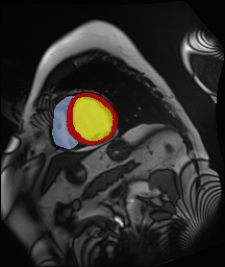

Medical data often exhibits long-tail distributions with heavy class imbalance, which naturally leads to difficulty in classifying the minority classes (i.e., boundary regions or rare objects). Recent work has significantly improved semi-supervised medical image segmentation in long-tailed scenarios by equipping them with unsupervised contrastive criteria. However, it remains unclear how well they will perform in the labeled portion of data where class distribution is also highly imbalanced. In this work, we present ACTION++, an improved contrastive learning framework with adaptive anatomical contrast for semi-supervised medical segmentation. Specifically, we propose an adaptive supervised contrastive loss, where we first compute the optimal locations of class centers uniformly distributed on the embedding space (i.e., off-line), and then perform online contrastive matching training by encouraging different class features to adaptively match these distinct and uniformly distributed class centers. Moreover, we argue that blindly adopting a constant temperature $\tau$ in the contrastive loss on long-tailed medical data is not optimal, and propose to use a dynamic $\tau$ via a simple cosine schedule to yield better separation between majority and minority classes. Empirically, we evaluate ACTION++ on ACDC and LA benchmarks and show that it achieves state-of-the-art across two semi-supervised settings. Theoretically, we analyze the performance of adaptive anatomical contrast and confirm its superiority in label efficiency.

翻译:医学数据经常呈现长尾分布和重度类别不平衡,这自然导致在对少数类别(即边界区域或罕见目标)进行分类时出现困难。最近的研究在长尾情况下通过装备医学影像的无监督对比标准,明显改进了半监督医学图像分割。然而,在标记的数据部分中,类别分布也极为不平衡,因此它们的表现如何仍不清楚。在本研究中,我们介绍一种采用自适应解剖对比度改进的对半监督医学分割行动的框架(ACTION++)。具体来说,我们提出了一种自适应监督对比损失,它首先在嵌入空间上计算出不同类别的优化位置(即离线),然后通过鼓励不同类别之间的特征与这些不同和均匀分布的类别中心相适应的在线对比匹配训练来进行自适应匹配。此外,我们认为,在长尾医疗数据中盲目采用常温度$\tau$不是最优的,因此通过一个简单的余弦计划来使用动态$\tau$来产生更好的多数类别和少数类别之间的分离。在实证方面,我们在ACDC和LA基准测试中评估ACTION++,并展示了其在两种半监督设置下的最新成果。从理论上讲,我们分析了自适应解剖对比度的性能,并证实了它在标签效率上的优越性。